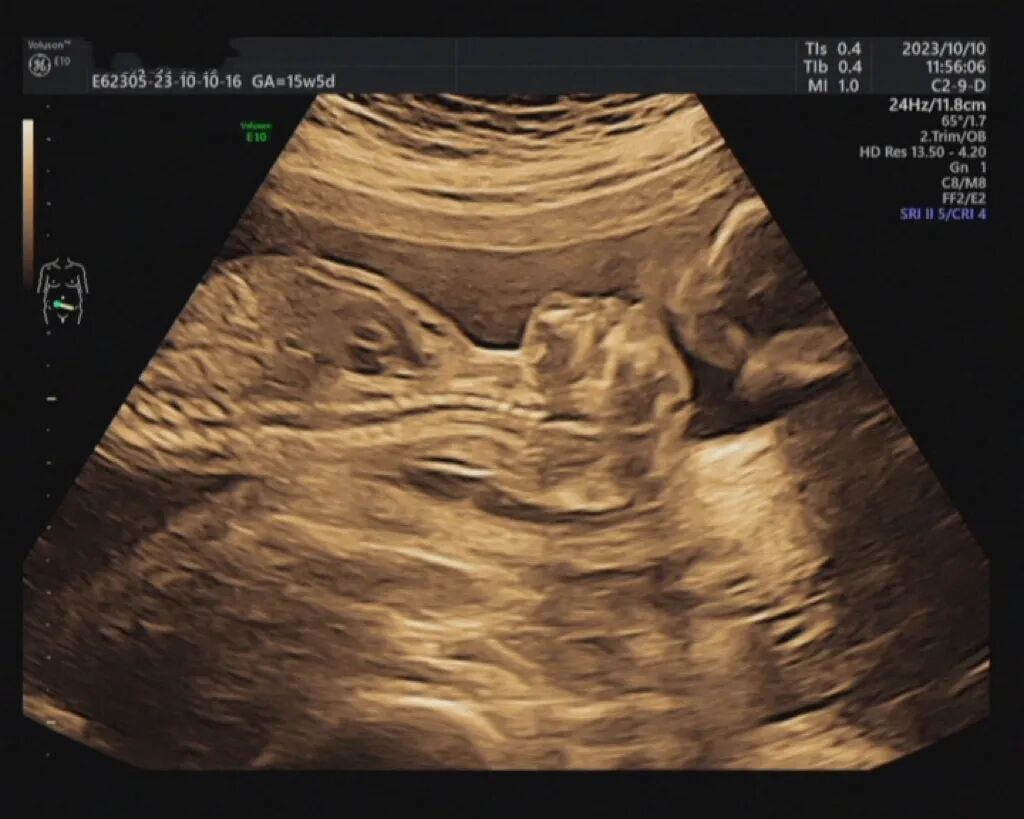

李女士是在妊娠12+4周时,在当地医院查出胎儿超声异常的,初次怀孕的她非常紧张、焦虑,随即慕名转诊至福建省妇幼保健院,复查针对性彩超结果提示:后壁胎盘,A胎发育AUA13w3d;B胎发育AUA13w3d,B胎露脑畸形,随访观察1周后复查。(露脑畸形:胎儿露脑畸形指的是胎儿颅骨缺失,脑组织只有脑膜覆盖的情况。)

等到妊娠15+5周,李女士再次复查彩超提示:A胎发育AUA16w4d;双侧脑室脉络丛囊肿;B胎发育AUA16w5d,无脑儿。